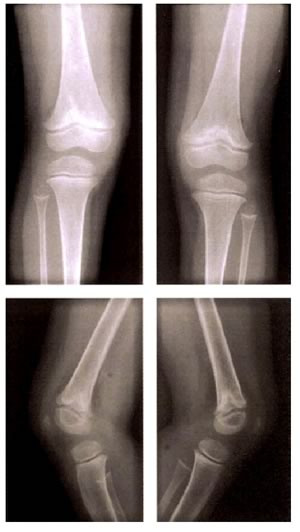

Quadro radiologico

Si osserva una rarefazione della trabecolatura ossea ed un allargamento delle metafisi con deformazione “a coppa”.

Le ossa maggiormente interessate sono appunto quelle a rapido accrescimento, come la tibia, il femore, il radio e l'ulna.